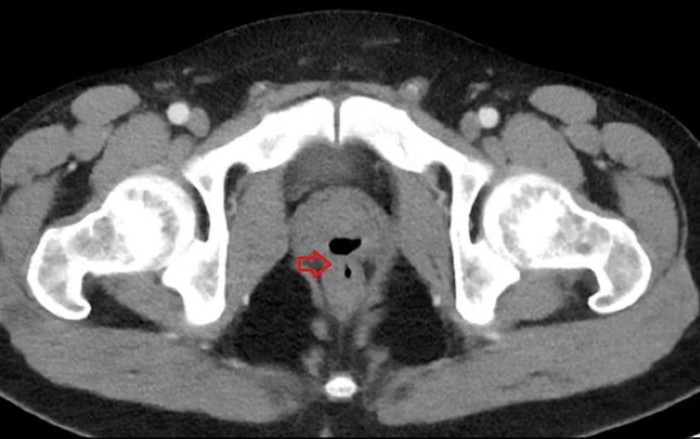

Sau khi kiểm tra, bác sĩ phát hiện có mối liên hệ bất thường giữa tuyến tiền liệt và trực tràng khiến nước tiểu, phân và tinh dịch cảu bệnh nhân ra khỏi cơ thể theo cách bất thường. Cụ thể, đây là một lỗ rò giữa trực tràng và tuyến tiền liệt, có thể là di chứng hậu phẫu thuật hoặc các bệnh viêm nhiễm như Crohn.

Trước đó, bệnh nhân chưa từng trải qua phẫu thuật hay chịu bất kỳ chấn thương nào ở trực tràng. Sau khi kiểm tra, bác sĩ kết luận nguyên nhân là do anh đã đặt một ống thông bàng quang trong 3 tuần hôn mê sau khi dùng cocaine từ 2 năm trước.